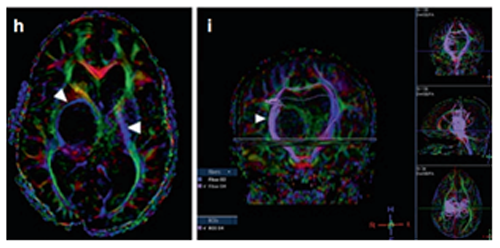

6岁男孩-WHO III级间变性星形细胞瘤

患者是一名6岁男童,症状为头痛、间歇性左上肢震颤。MRI(FLAIR序列)显示一个两侧丘脑肿瘤,右比左大,尾状核的右头部也参与其中。脑室轻度增大,膈膜水肿,肿瘤内部囊肿。因此,Rutka教授为其先行左额部内窥镜活检和鼻中隔造瘘术,再行左枕脑室-腹腔分流术。

(图8)

组织病理诊断为WHO III级间变性星形细胞瘤,H3K27M、p53、BRAF V600E突变免疫阴性。MIB-1增殖指数为40%。至此,Rutka教授为患儿制定了周密的综合治疗方案,患儿开始同时接受替莫唑胺(TMZ)和放射治疗(59.4 Gy),并接受累计剂量为200 mg/m2的12个周期的持续替莫唑胺治疗。该男孩在确诊后15个月放射学表现稳定,症状也得以缓解,生活质量有所提升。